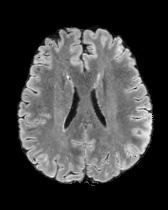

We also test our approach on healthy samples. Ideally, we would like our generative process to act as the identity function when given a normal image as input. Some examples are shown in Figure 6, where we can observe that the changes introduced by our sampling technique are relatively minimal and Dif-fuse preserves the structure and general appearance of the images.